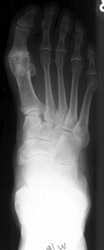

There are three patterns of involvement of psoriatic arthritis in the feet.

First pattern primarily involves DIP, PIP, and MTP. Second pattern is single

ray involvement where all the joints of one digit are involved while other

fingers are spared. The third pattern is similar to rheumatoid arthritis distribution.

Fusiform soft tissue swelling involving a single ray can occur giving the

appearance of 'sausage digit'.

| Joint | Frequency |

| 1st interphalangeal | ++ |

| 2nd - 5th interphalangeal | + | |

| 1st Metatarsophalangeal | +++ |

| 2nd-5th Metatarsophalangeal | +++ |

| Tarsometatarsal | - |

| Chopart | - |

| Arthritides of the Foot |

Psoriatic Arthritis |